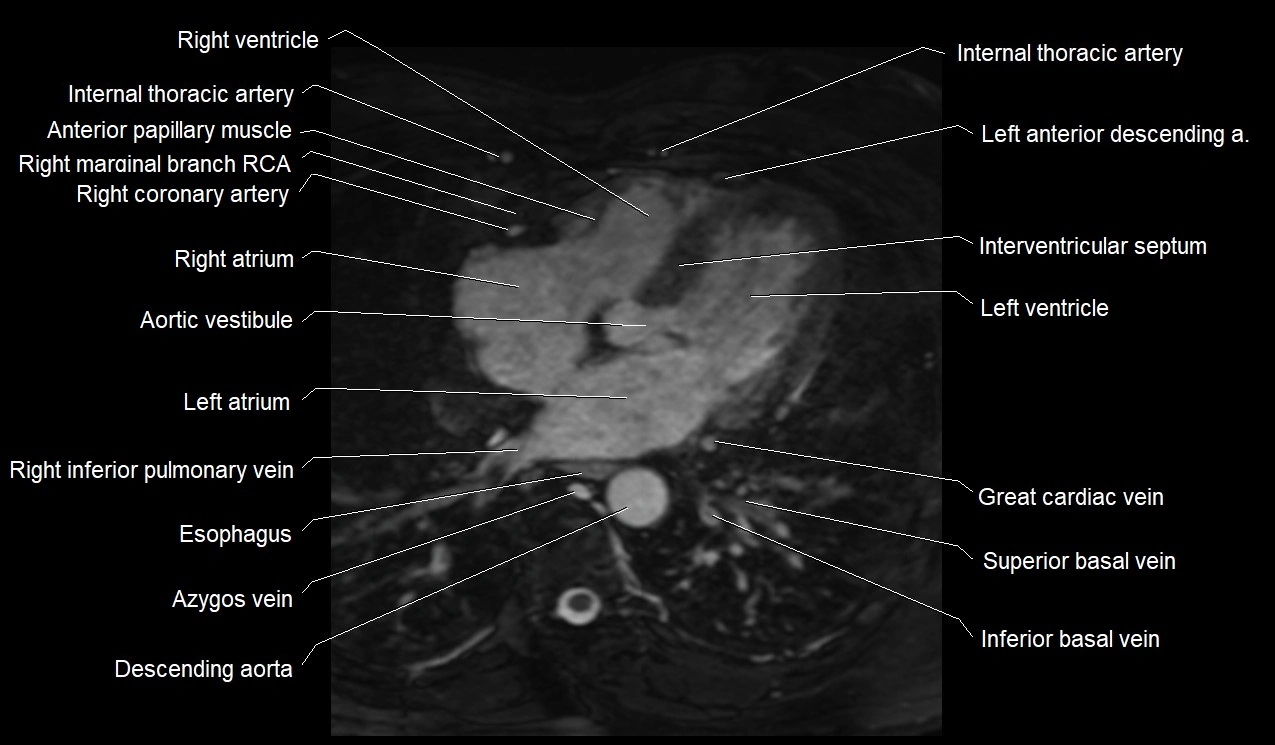

MRI image